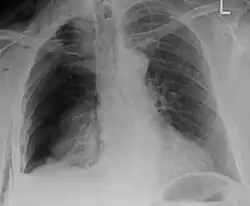

Plain X-rays often pick up displaced fractures but often miss undisplaced fractures.[13] CT scanning is generally able to pick up both types of fractures.[13]

Illustration showing rib fracture at 3rd, 4th and 5th rib -

Right sided pneumothorax and rib fractures -